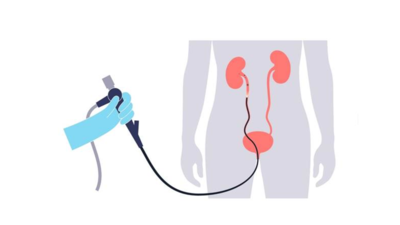

МОЧЕКАМЕННАЯ БОЛЕЗНЬ

Информационный раздел по МКБ